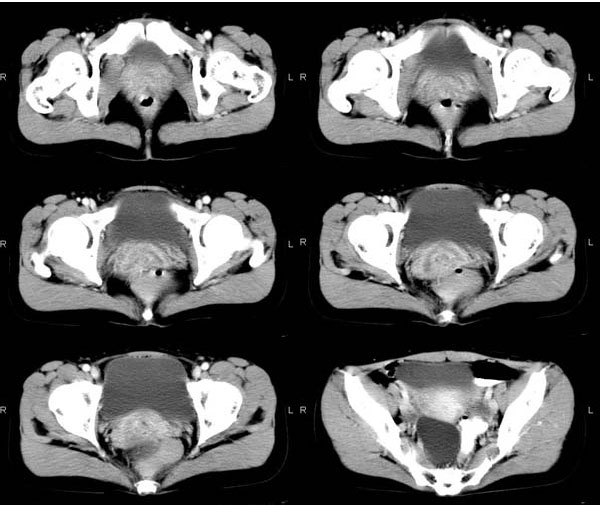

(结果公布:http://www.radida.com/bbs/forum.php?mod=viewthread&tid=57307) 患者女性,39岁,下腹部不适2年,多次b超提示盆腔囊性占位(最大径约约6.1 cm),多考虑卵巢囊肿。一周前德国妇科专家来我院指导工作 ...

术中诊断:右侧输卵管囊肿。